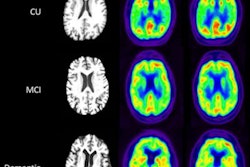

PET images acquired from both the standard scanning time of 20 minutes and reduced scanning times of one, two, five, and 10 minutes were reconstructed by the MCDNet-2 denoising model for each patient and then compared. The quality of the PET images was quantitatively evaluated using objective metrics, while two radiologists performed subjective evaluations using a qualitative 5-point grading system.

Visual comparison of reduced scan time PET images before and after denoising by MCDNet-2, with those of the normal scanning time of 20 minutes.The denoised results of the one-minute and two-minute PET images were overly smooth and blurry, the researchers reported. The denoised results of the five-minute and 10-minute PET images, however, showed a high similarity with the ground truth 20-minute PET images.